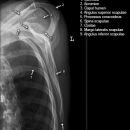

Schulter a.p. (Schultergelenk nach Grashey)

Beurteilungskriterien

- Außenrotation ->Tuberculum majus lateral randbildend, Innenrotation ->Tuberculum minus medial randbildend

- Gelenkspaltweite 4-6 mm

- Weite des subacromialen Raumes exakt nur in der 10 – 15° nach kaudal angulierten Aufnahme bestimmbar ("Morrison, Outlet View")! Normalerweise 1 - 1,5 cm, < 6 mm -> wohl pathologisch, Impingment röntgenlog. wahrscheinlich, Cave. rein klinische Diagnose!

- Normvarianten: Os glenoidale (akzessorischer Ossikel kaudal des Glenoids), persistierende Akromion- oder Korakoidapophyse, entwicklungsbedingte Pfannenranddefekte